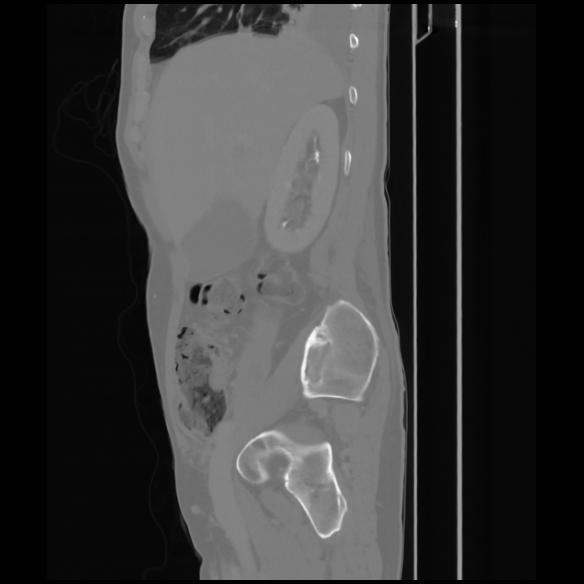

7 CUERPO,CE,Sagittal,3.000,CUERPO,Sagittal,